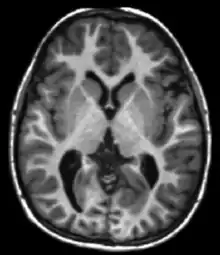

| Spin echo | T1 weighted | T1 | Measuring spin–lattice relaxation by using a short repetition time (TR) and echo time (TE). |

Standard foundation and comparison for other sequences |